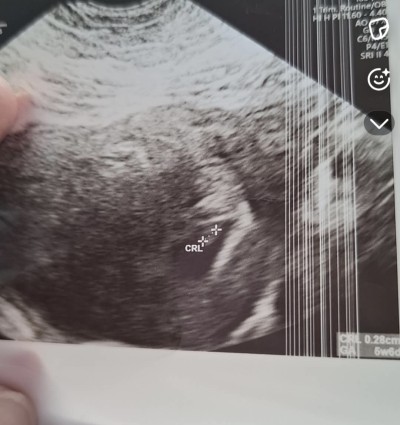

Kızlar ben son regl tarihmden hesapla 7+4de gittim doktora bebek oluşmuş kese çapı 15mm kalp atışı yoktu 10 gün sonra gel dedi geç döllenme ola bilir bebek daha 5 haftalık dedi dün gittim 8+5 olyor son adet tarihimden hesaplandığında yine de kalp atışını duyamadık 4 gün sonra gel dedi son kes dinleyelim kese boyum hocamın dediğine göre 18mm olmuş bebek de 5mm olmuş 7 mm kadar duyulur duyulmazsa alıcaz dedi ama ultrosan fotoda aşağıda kese ölcüm 33mm çıkıyor böyle bişey başına gelmiş var mı

Gebelik haftası 8+6